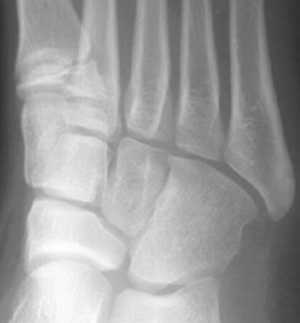

Skeletal Trauma > Foot & Heel > Foot & Heel Quiz

What fracture is shown here?